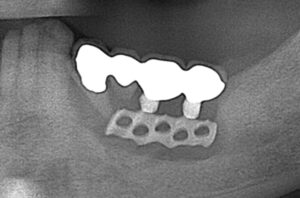

ブレードインプラント

こちらが1960年代に使われた板状で窓が開けられているブレードインプラントの実際の写真になります。

レントゲン像では大きな骨吸収が見られます。

来院時には、揺れが大きく、痛みもあったため撤去を行いました。

現在は吸収されていた骨も治癒し、元々のインプラント部位は入れ歯を作製し使用されています。